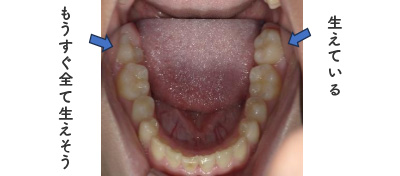

12歳臼歯と言われる前から7番目の歯が上下左右生えている、またはもうすぐ全部生えそう・・・というタイミングですと矯正治療がスタートできますが、内容は成人の矯正治療と同じになります。